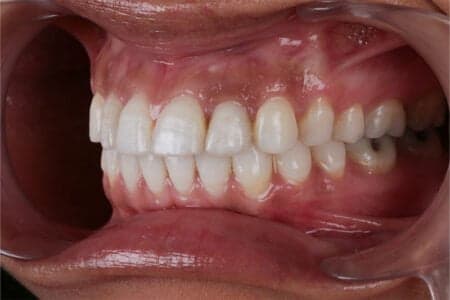

Desde muy pequeña han confiado en nosotros para tratar la malposición que tenía y la ausencia de los dientes vecinos a los incisivos centrales superiores que simplemente no le habían salido.

Con el tratamiento de ortodoncia corregimos posición y abrimos huecos para poder colocar implantes. Tras reponer la piezas perdidas con implantes dentales y dientes en el día de la cirugía realizamos blanqueamiento zoom para finalizar su caso.